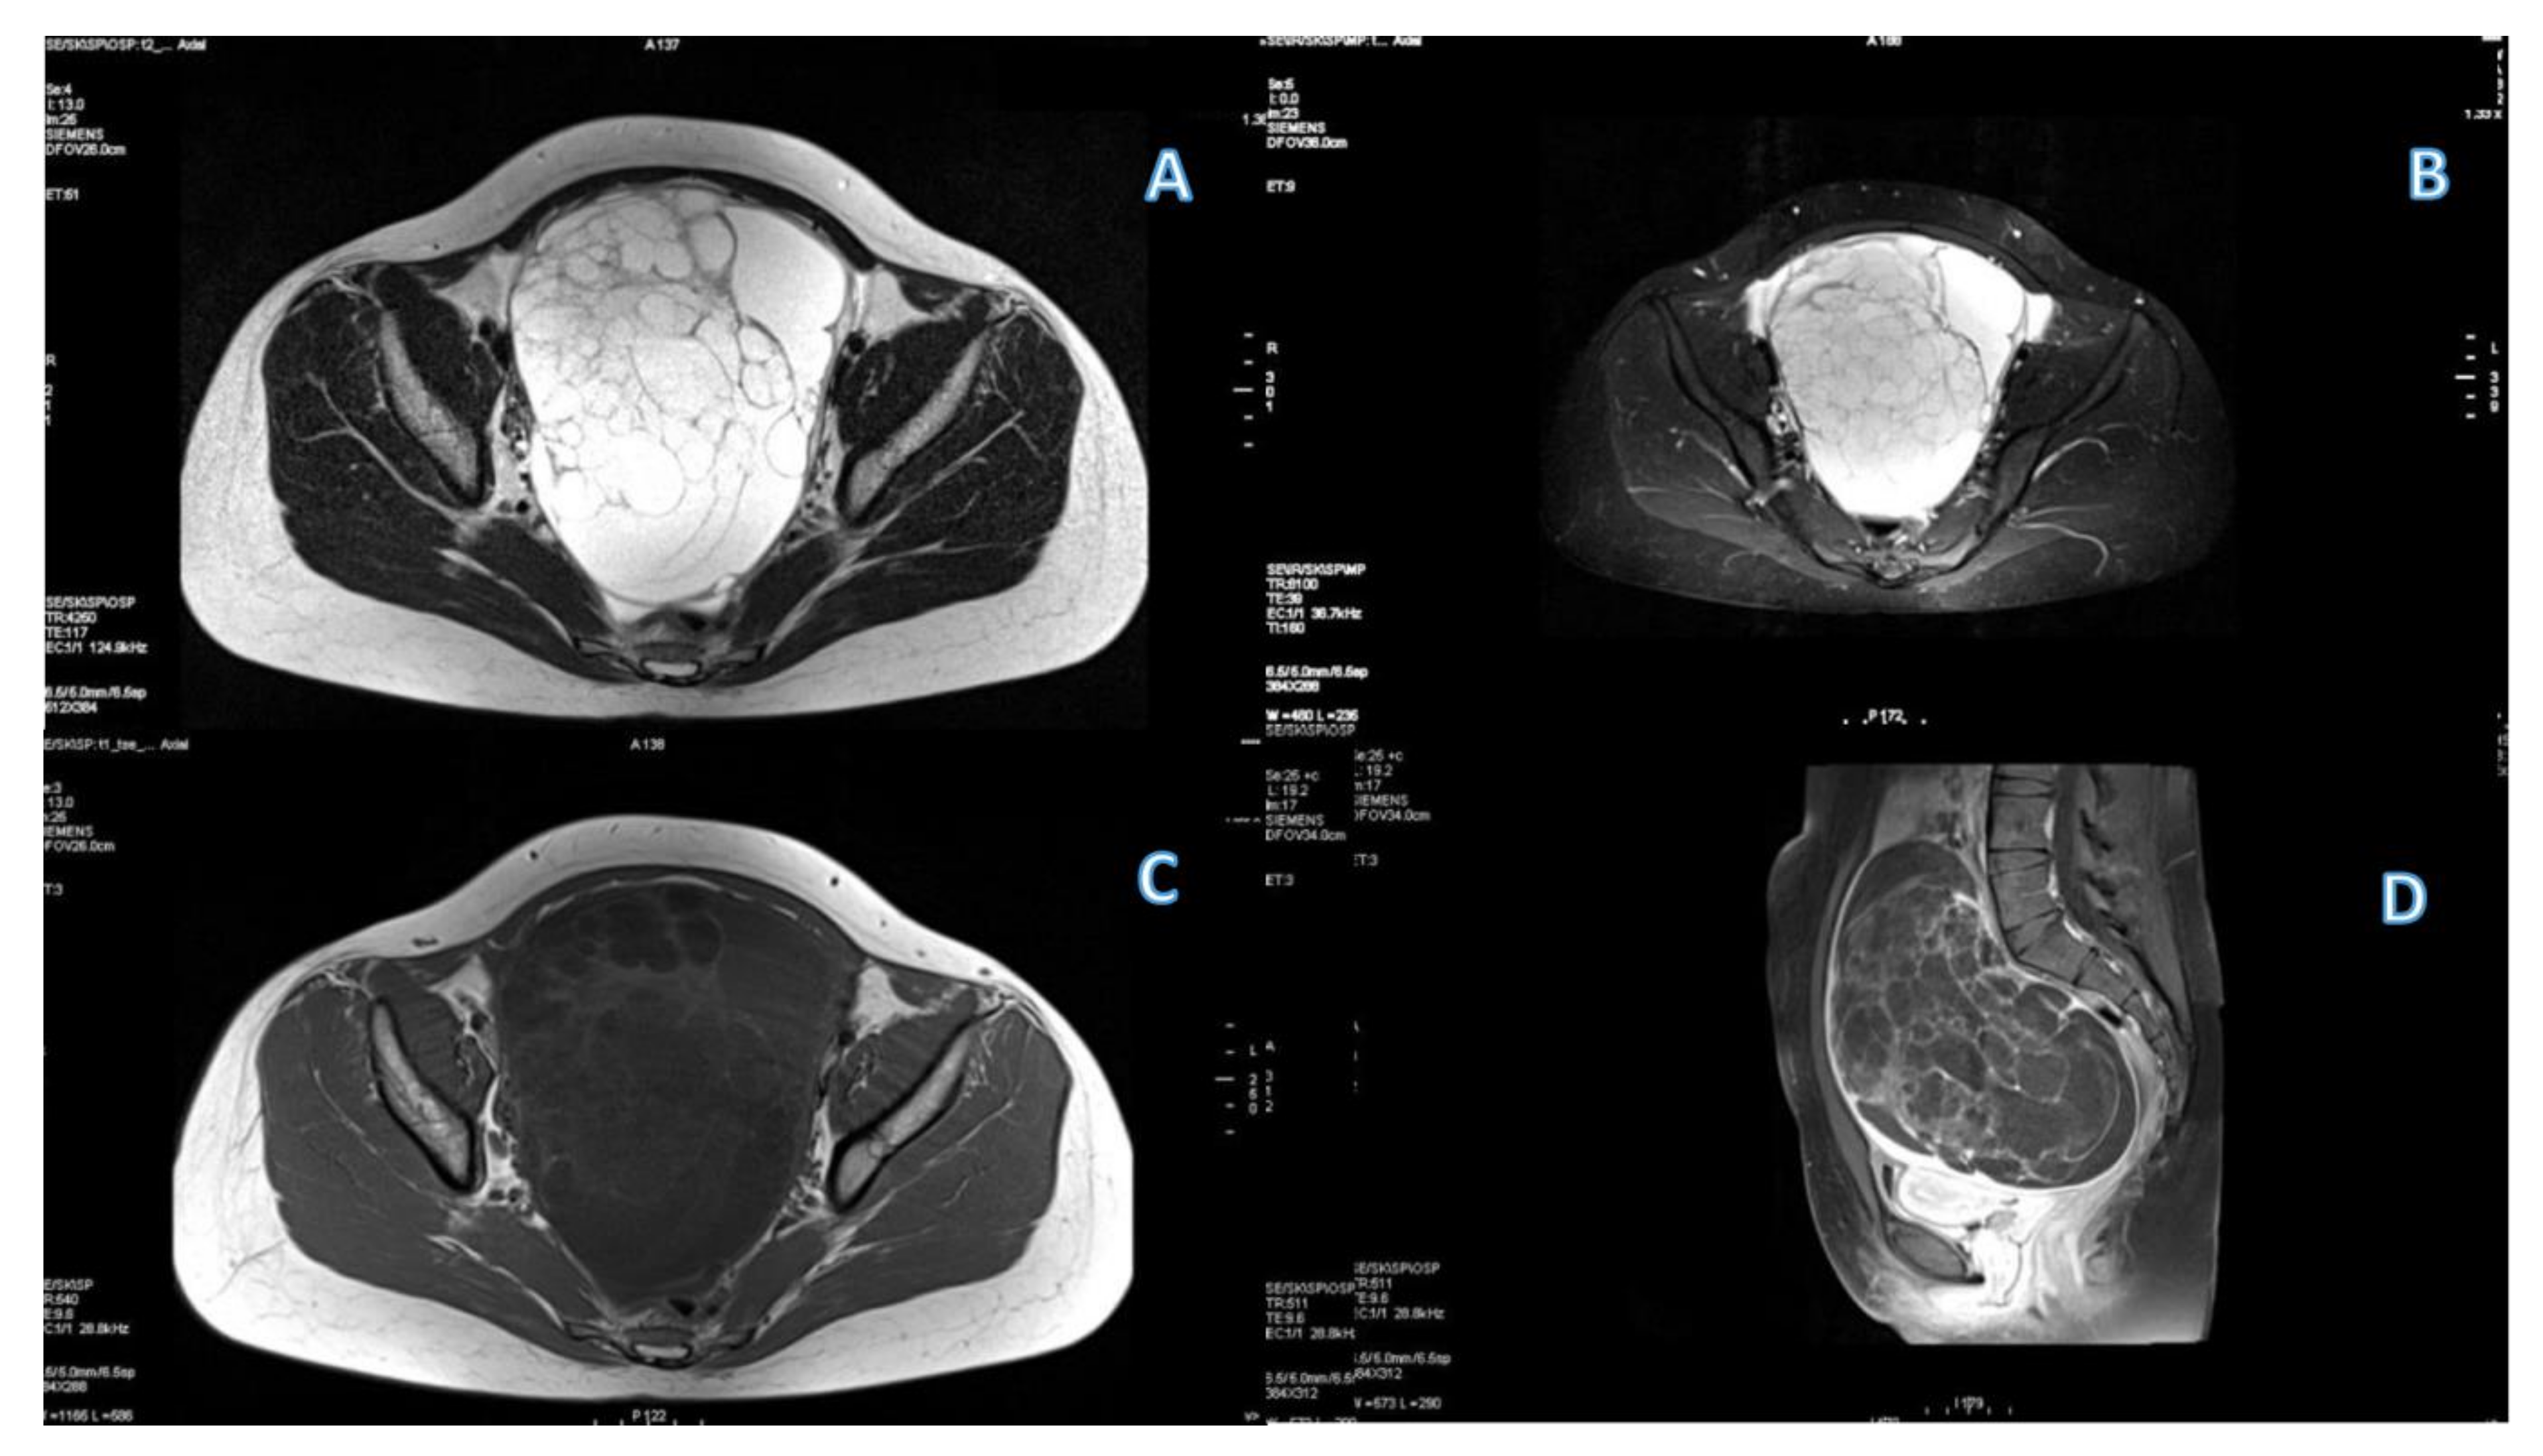

2.2. MRI Protocol

3.1. Primary Tumor DWI